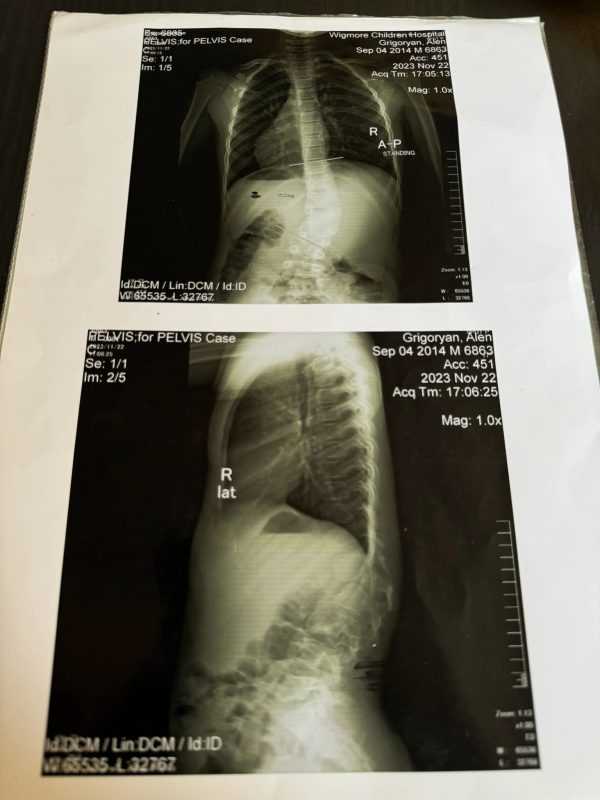

Իմ լավ ընկերներից մեկի բալիկը՝ 10-ամյա Ալենը, ում մոտ ախտորոշվել է ողնաշարի գոտկային հատվածի բնածին սկոլիոզ, ունի մեր բոլորիս օգնության կարիքը:

Ստորև տեղադրում եմ երեխայի լուսանկարը, աշխոտորոշումը, անհրաժեշտ գումարի մասին տեղեկանքը (նշված է զուտ վիրահատության և իմպլանտների գինը) և ընտանիքի հաշվեհամարները: